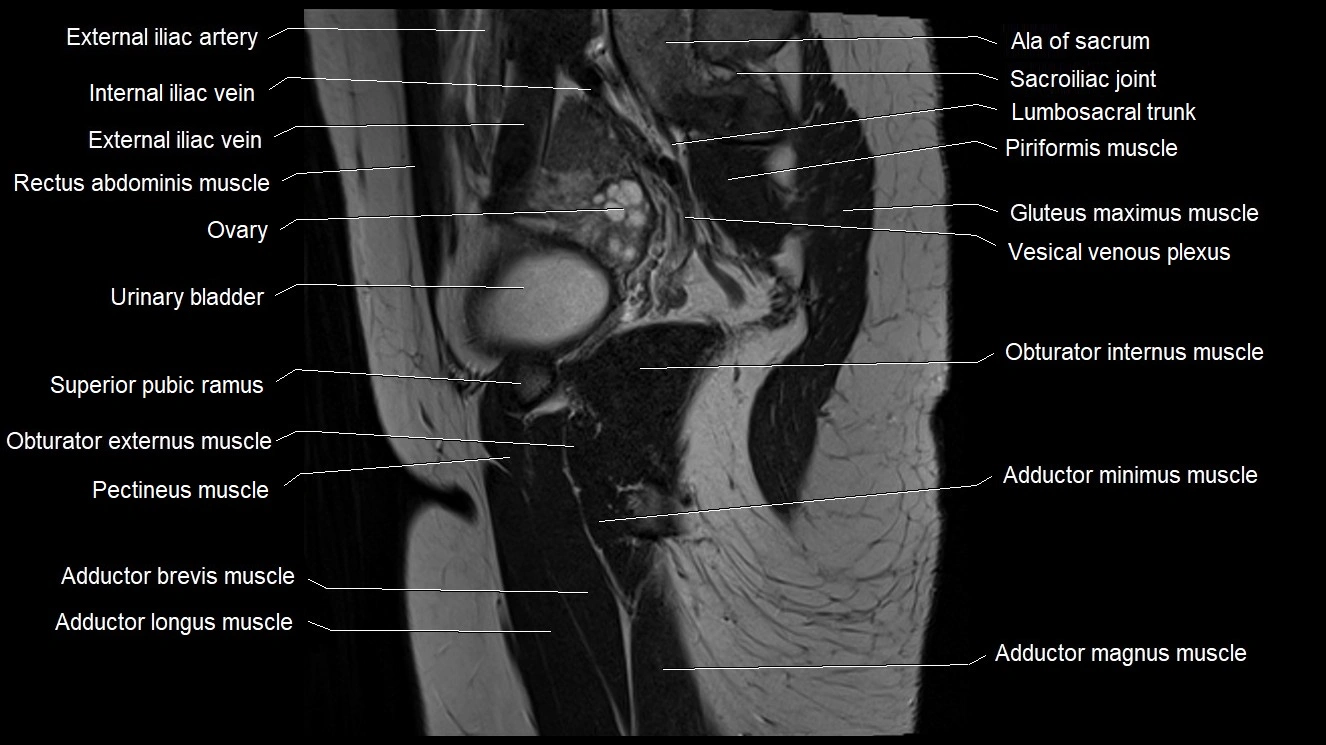

- Adductor brevis muscle

- Adductor longus muscle

- Adductor magnus muscle

- Adductor minimus muscle

- External iliac artery

- External iliac vein

- Ilium bone

- Lumbosacral trunk

- Obturator externus muscle

- Obturator internus muscle

- Ovaries

- Pectineus muscle

- Sacroiliac joint

- Superior pubic ramus

- Urinary bladder

- Vagina